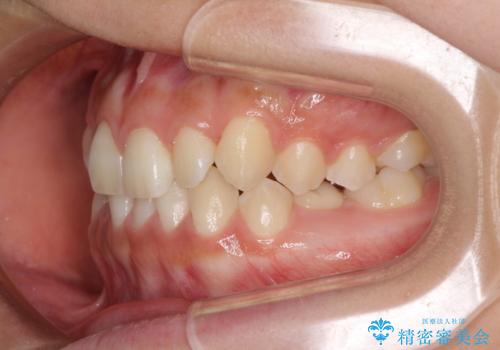

矯正治療が終わるタイミングに合わせてインプラントの埋入を行っていたので、矯正治療を終了すると同時にセラミック補綴治療を行えました。

短期間でしっかりと治療を終えることができました。